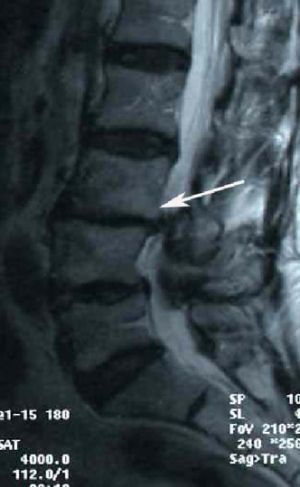

2. Истмический спондилолистез (спондилолиз)

Слабость суставных отростков, которая может быть результатом их перелома (чаще в детстве или подростковом периоде) ведет к соскальзыванию вперед вышележащего позвонка. Это наиболее часто выявляемый листез среди молодых, обычно встречается на уровне L5-S1, ведущий к компрессии нервных структур разросшейся соединительной тканью в месте перелома. Некоторые авторы считают причиной развития истмического листеза не однократную травму, а повторяющуюся много раз. Большинство пациентов с истмическим листезом не достигают высоких степеней соскальзывания позвонка и долгое время не предъявляют жалоб на боли.